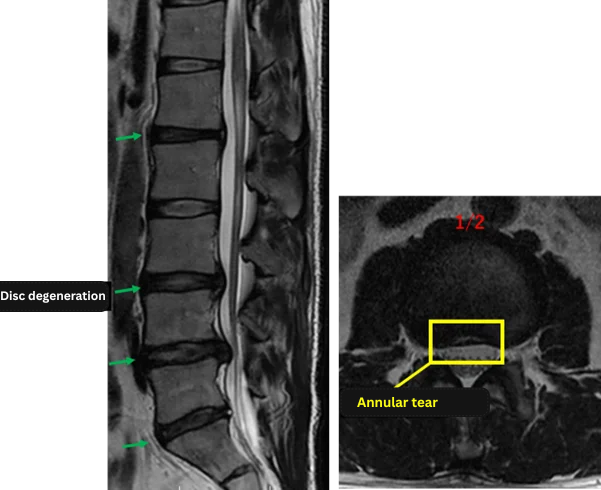

L1/2: Disc degeneration, disc bulging, annular tear

L2/3: No abnormality

L3/4: Disc degeneration, central disc herniation

L4/5: Mild disc degeneration, disc herniation

L5/S: Disc degeneration, disc bulging, annular tear

The above findings were also observed on the imaging.

Disc degeneration, disc bulging, and annular tears observed at L1/2, L3/4, L4/5, and L5/S were considered highly likely to be the primary causes of the patient’s symptoms.